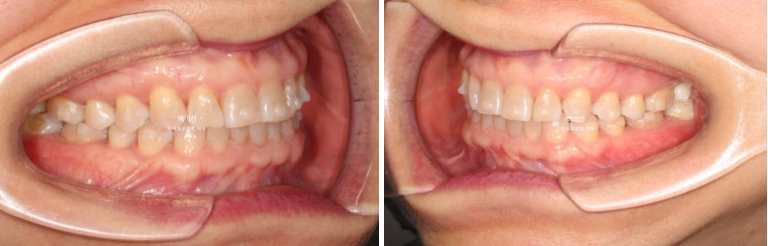

25.02~25.08

25년 2월, 교정치료를 위해 내원한 환자분입니다.

위 앞니 사이가 점점 벌어지고 아래 앞니는 점점 틀어진다 라는 이유로 오셨습니다.

25.02

앞니가 깊게 물리는 과개교합이 보입니다.

파란 화살표는 벌어진 틈을 레진으로 메꿔놓은 곳 입니다.

인비절라인 익스프레스로 과개교합 개선이 가능합니다.

앞니 교합이 얕아지면서 윗니에 가려 잘 안 보이던 아래 앞니가 이제 절반 이상 보이게 되었습니다.

레진으로 메꿔놓았던 틈은 교정으로 완벽하게 사라졌습니다.

앞니 뿐 아니라 송곳니가 튀어나왔던 부분도 배열이 개선이 되었습니다.